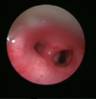

The commonly misleading history given by the parents is that the child may have had a trivial trauma or an insect bite. However, for the clinician the golden rule should be ‘Any acute scrotum is testicular torsion unless proved otherwise’. Investigations like ultrasound and color doppler may be done to help in the diagnosis. However, in the event of any doubt, it is safest to do a surgical exploration of the scrotum. The other uncommon causes of acute scrotum are acute epidydymo orchitis, scrotal abscess, idiopathic scrotal oedema and torsion of appendix of the testis. ●

Acute Scrotum (Right scrotal Abscess)

Acute Scrotum